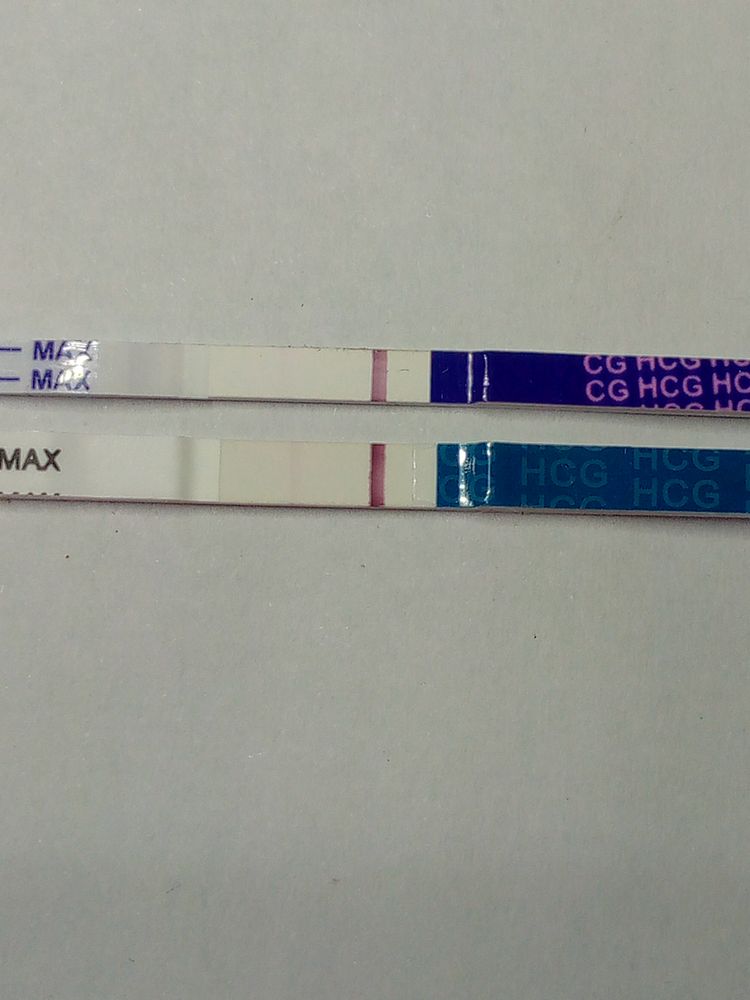

Эх совсем недавно я тусила на этом сообществе а сейчас моё чудо рядом со мной.. Но история не обо мне. Подруга 6 раз сделала перенос и хочется ваше коллективное мнение. Конечно понимаю что рано, но мы так устали ждать.. Сейчас 4 дпп посмотрите я одна вижу полоску уколов хгч не было в поддержке